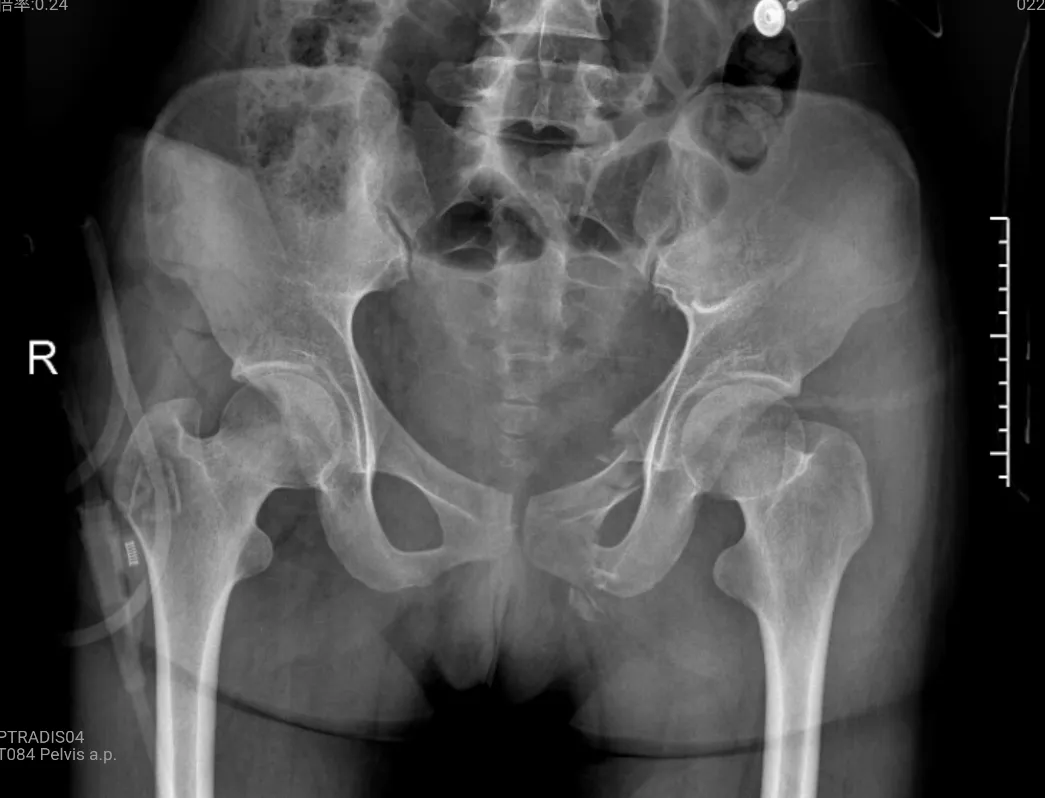

某天,22歲的小陳被120緊急送至浙江省榮軍醫(yī)院急診,據(jù)同行的朋友告知,她不慎從九樓跌落至八樓平臺(tái)。雖僅有一層,但巨大的沖擊力讓小陳的頭面部、腰背、手腕以及骨盆傳來陣陣劇痛,且左上肢和腰背無法動(dòng)彈。急診CT檢查發(fā)現(xiàn),患者從眼眶、上頜、腰椎到左側(cè)髂骨、恥骨、尾骶骨存在多處骨折及錯(cuò)位。

與此同時(shí),醫(yī)院創(chuàng)傷骨科團(tuán)隊(duì)積極響應(yīng)救治,根據(jù)患者的軟組織傷情和骨折程度制定出了手術(shù)方案——借助專業(yè)影像設(shè)備定位骨折部位,通過微小切口完成股骨、恥骨、橈骨等位置的骨折復(fù)位與固定。

針對(duì)小陳這樣的案例,使用的經(jīng)皮恥骨支螺釘內(nèi)固定術(shù)是一種髓內(nèi)固定技術(shù),在治療骨盆前環(huán)損傷中得到了越來越廣泛的應(yīng)用,常用于恥骨上支骨折和髖臼前柱骨折。經(jīng)過實(shí)踐分析,這是治療單側(cè)恥骨骨折的最佳治療方式,具有手術(shù)創(chuàng)傷小、術(shù)中出血量少、固定強(qiáng)度大、并發(fā)癥少及功能恢復(fù)快等優(yōu)點(diǎn)。